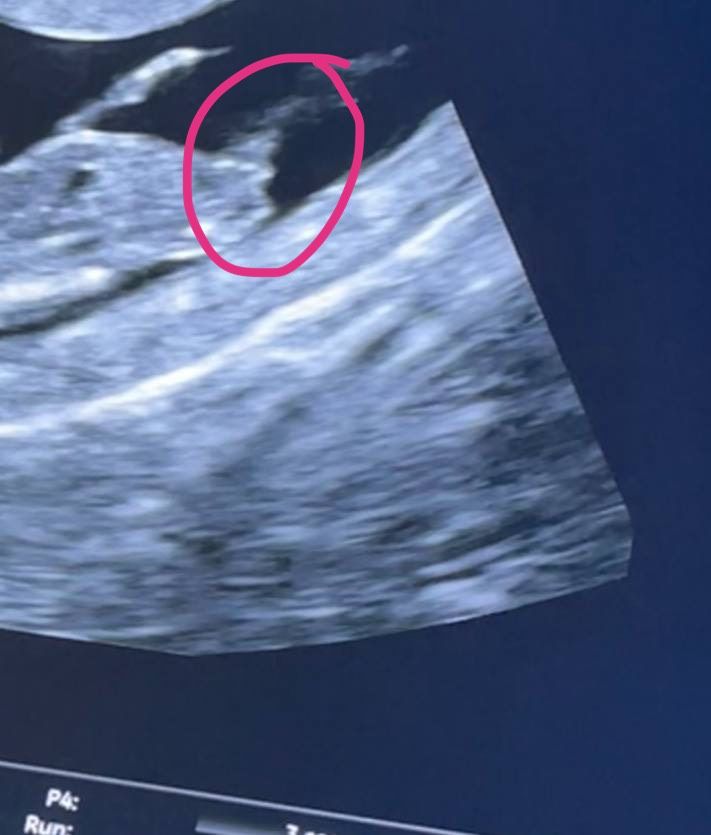

ну и ещё разок скину вам нашу фотку)) погадаем))